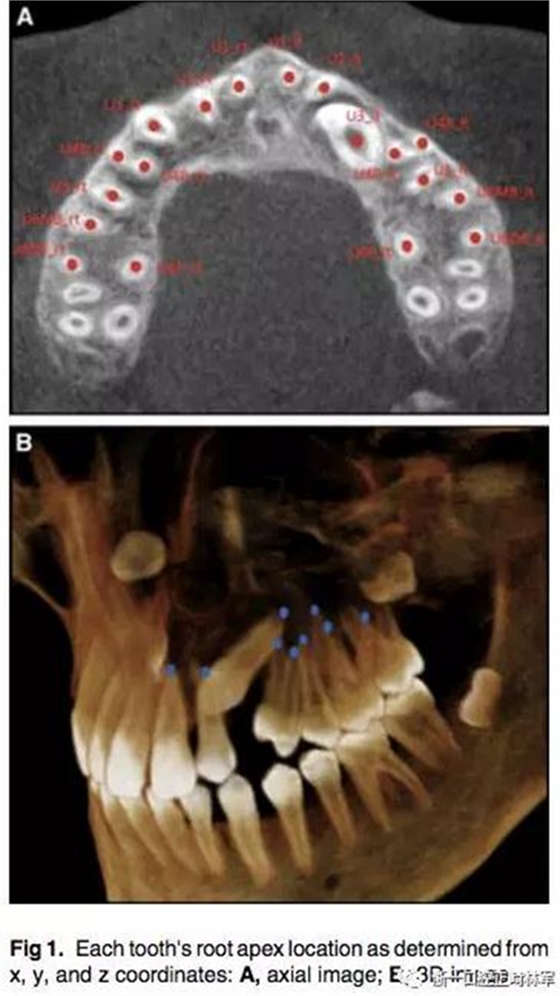

通過CBCT來確定尖牙牙根的具體位置,以x,y,z三維坐標(biāo)表示。我們定義在面中線上,鼻根點作為鼻額縫在額骨上的最前點,CBCT掃描儀與腭平面水平。我們用3個標(biāo)志點(前鼻棘點,兩側(cè)腭大孔的中心點)來定位腭平面,將鼻根點坐標(biāo)定為(0,0,0),以此確定上頜牙齒根尖點的x,y,z的坐標(biāo)。由于上頜前磨牙和磨牙有2-3個牙根,因此將多個牙根的中心點作為根尖點。見Fig1.